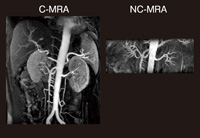

IFIR法は,バックグラウンドと静脈の信号を落とすインバージョンパルスを印加し,その後にインフロー効果で動脈の血流を描出する方法である。選択性に優れ,撮像領域を限れば動脈,静脈を問わず描出できるほか,比較的高いSNRを得られることが特長である。血流が遅いと描出範囲がやや狭くなるという課題はあるが,図2ではFlow Prep法に比べて血管が末梢まで描出されている。また,右腎動脈起始部の狭窄も認められる。

図2

図2 右腎動脈狭窄